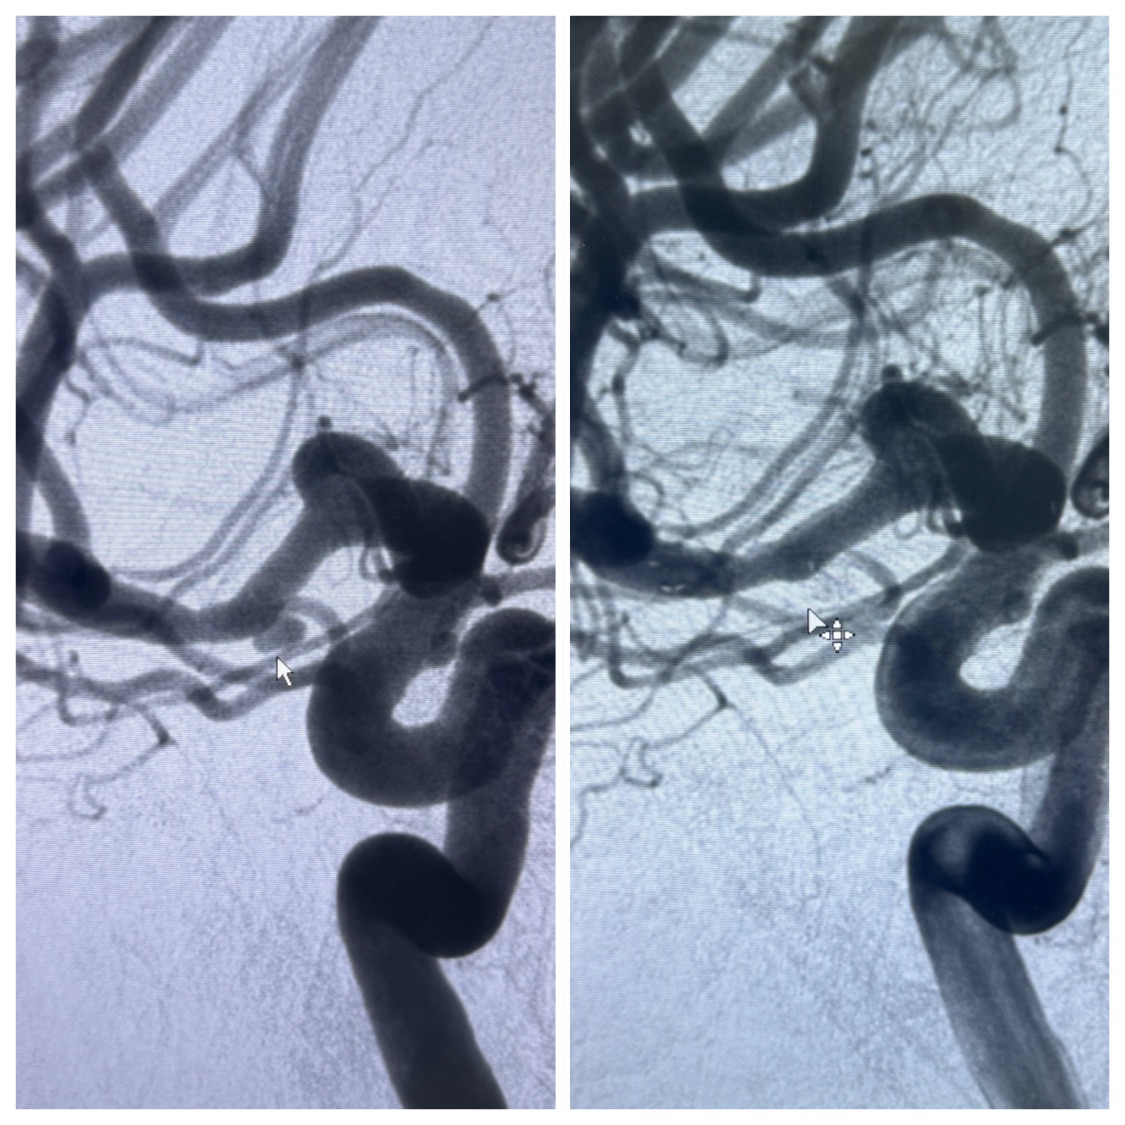

2023-11-24DSA:右侧大脑中动脉下干起始部动脉瘤,约2.3*2.5mm,形态规则

2023-12-04全麻下行支架辅助治疗

S-AB4-20mm